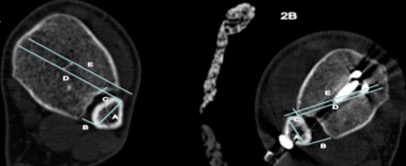

Con la TC postoperatoria con cortes axiales se establecieron criterios de reducción sindesmal, siempre comparados con el lado contralateral sano. Las medidas se tomaban a un centímetro del plafón tibial. Se determinan las distancias anterior y posterior del peroné como una línea que une su borde anterior y posterior con la incisura tibial respectivamente (Figura 2). Ambas líneas eran perpendiculares a la línea antero-posterior, definida como aquella que une los bordes anterior y posterior en la zona más ancha del peroné. Se continuó la línea de la distancia fibular anterior y se trazó una paralela cortando el borde anterior de la incisura (línea E). La diferencia entre ambas líneas era la distancia de traslación anterior (Figura 2) [19]. Así mismo, se compararon las medidas con el lado contralateral y las diferencias, a su vez, se separaron en dos categorías de mala reducción, >1 mm o >2 mm.

Figura 2. Mediciones comparativas para evaluar la reducción sindesmal. Extraída del artículo de Davidovitch et al. A) línea anteroposterior. B) distancia articular posterior. C) Distancia articular anterior. D) Extensión de la línea anterior. E) Línea incisural anterior. Distancia D-E) Traslación anterior.

Figura 2